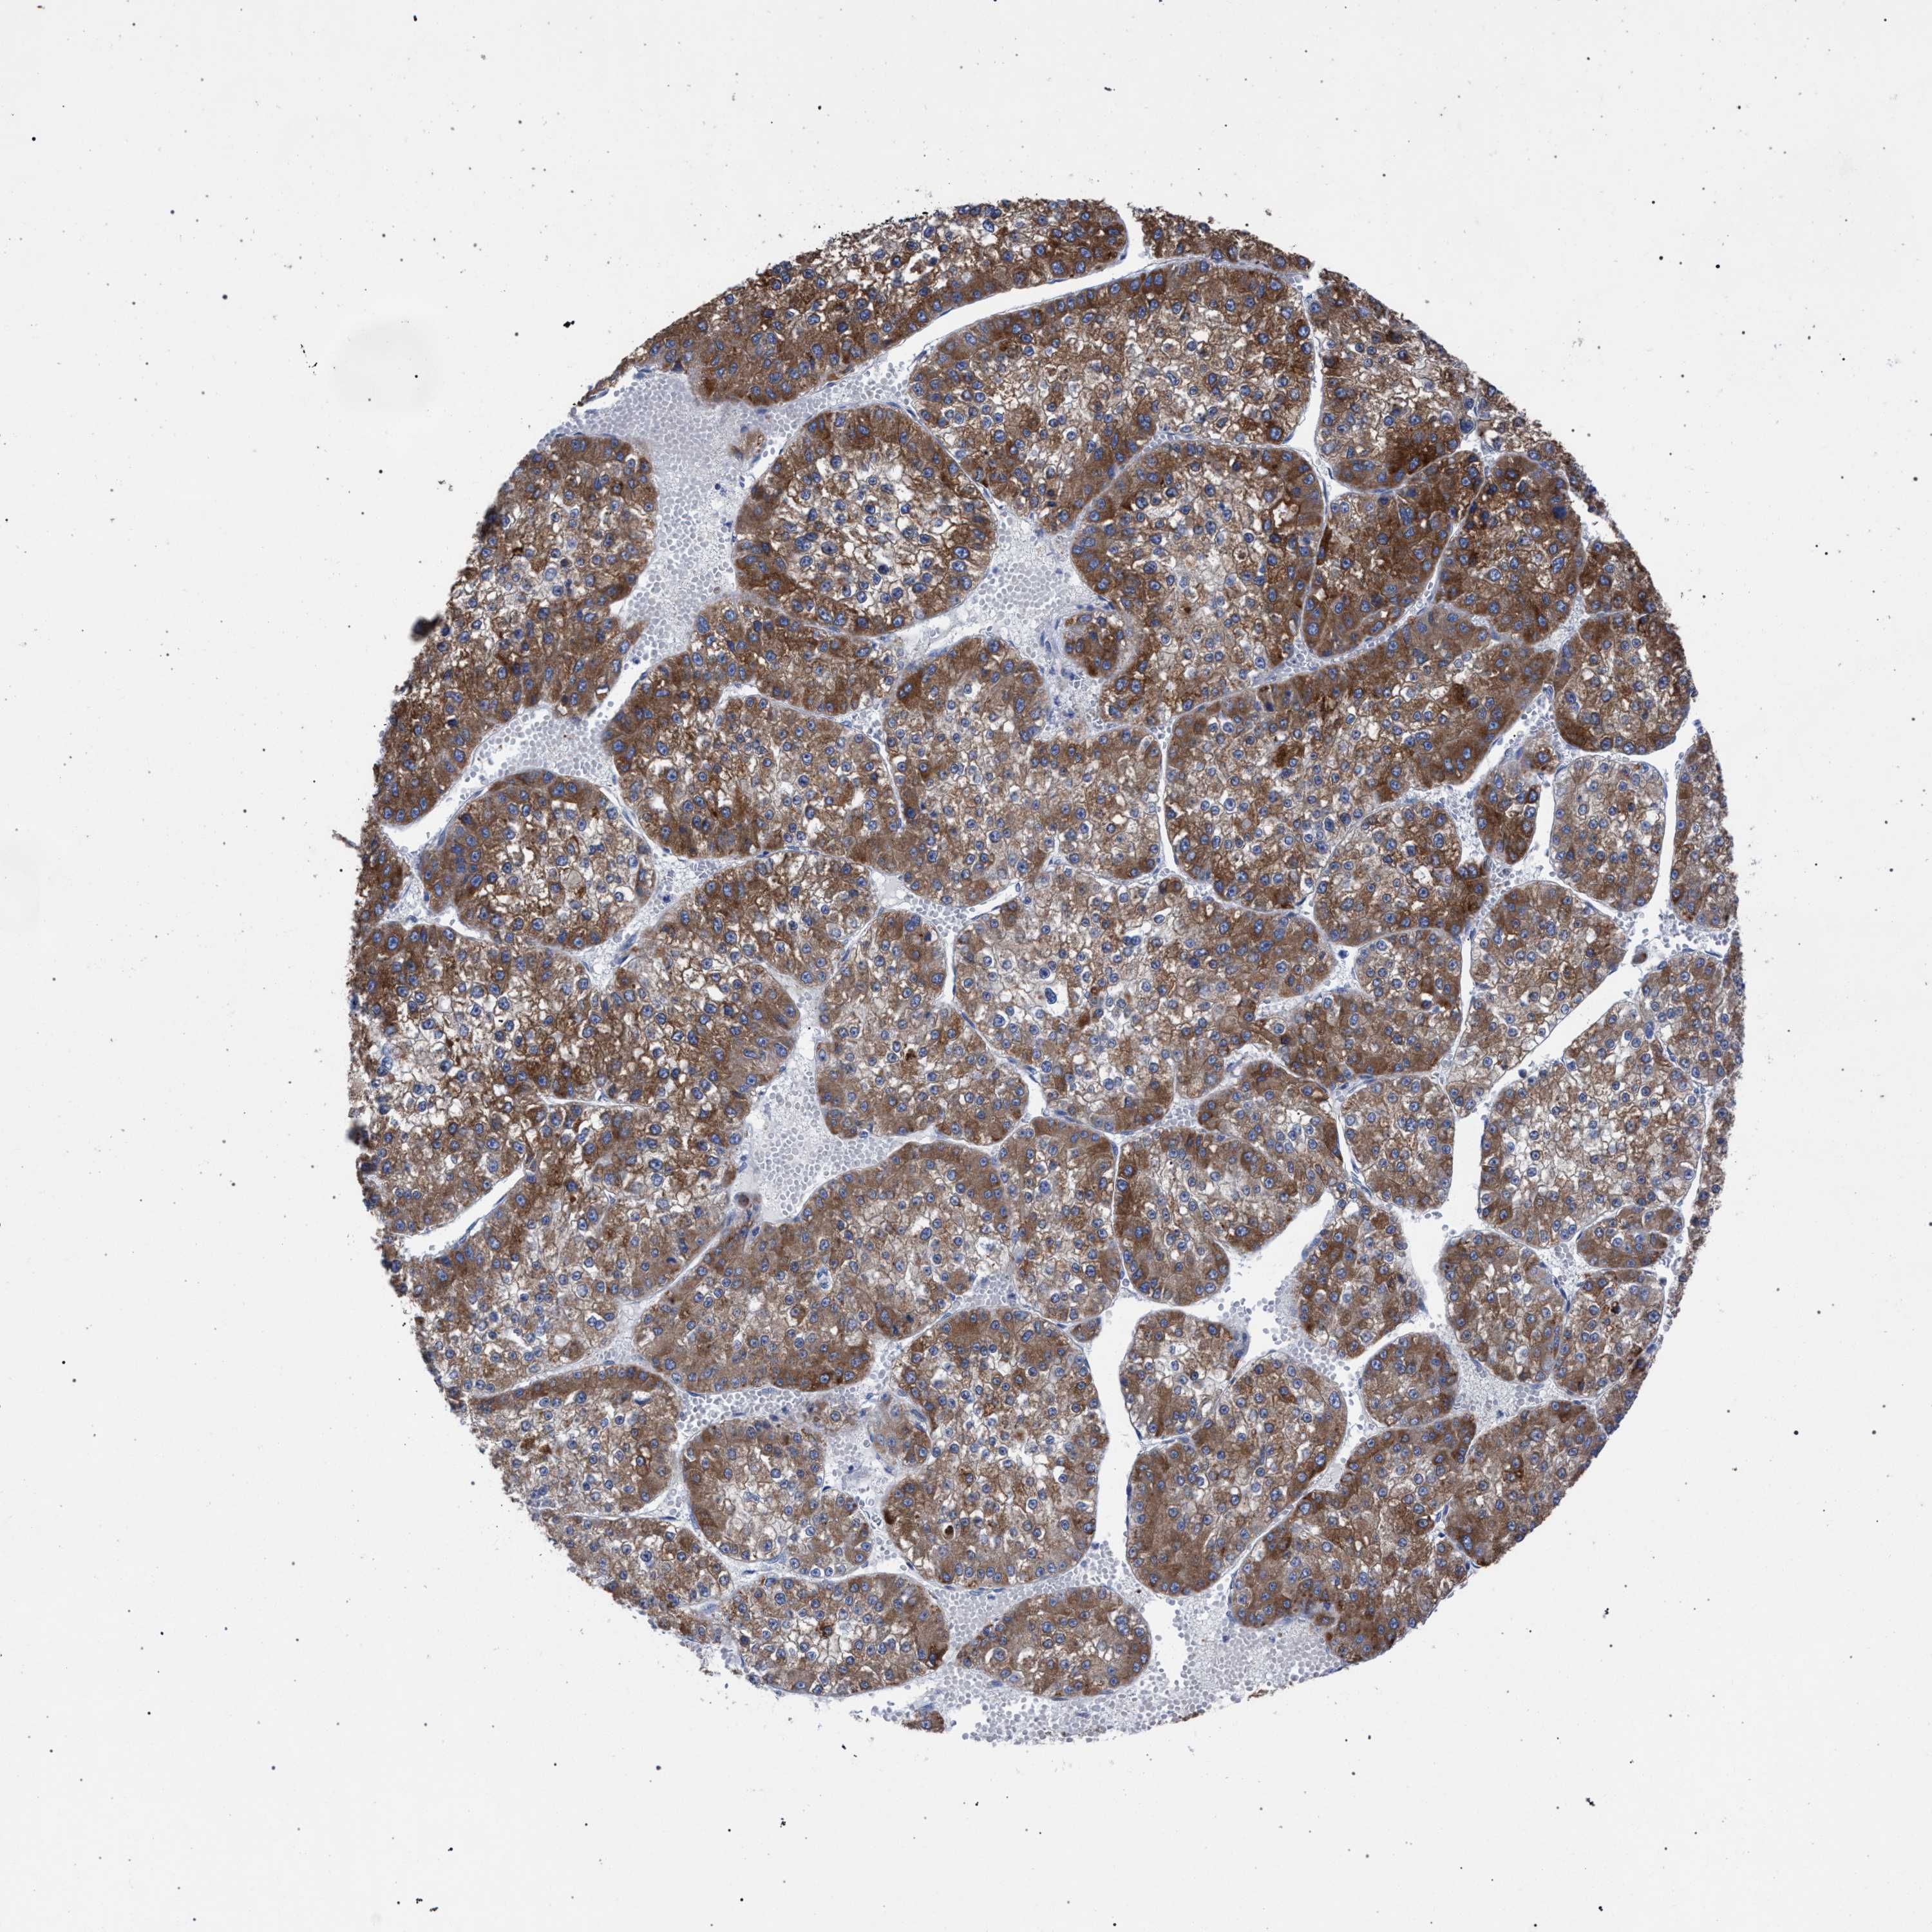

LIVER CANCER - Protein expressioni

A mouse-over function shows sample information and annotation data. Click on an image to view it in a full screen mode. Samples can be filtered based on level of antibody staining by selecting one or several of the following categories: high, medium, low and not detected. The assay and annotation is described here.

Note that samples used for immunohistochemistry by the Human Protein Atlas do not correspond to samples in the TCGA dataset.

Antibody stainingi

Antibody staining in the annotated cell types in the current human tissue is reported as not detected, low, medium, or high, based on conventional immunohistochemistry profiling in selected tissues. This score is based on the combination of the staining intensity and fraction of stained cells.

Each image is clickable and will lead to virtual microscopy that enables deeper exploration of all samples and also displays staining intensity scores, fraction scores and subcellular localization as well as patient and tissue information for each sample.

Antibody HPA000904

Antibody HPA021476

Staining

High

Medium

Low

Not detected

Intensity

Strong

Moderate

Weak

Negative

Quantity

>75%

75%-25%

<25%

None

Location

Nuclear

Cytoplasmic/membranous

Cytoplasmic/membranous,nuclear

Carcinoma, Hepatocellular, NOS

Cholangiocarcinoma